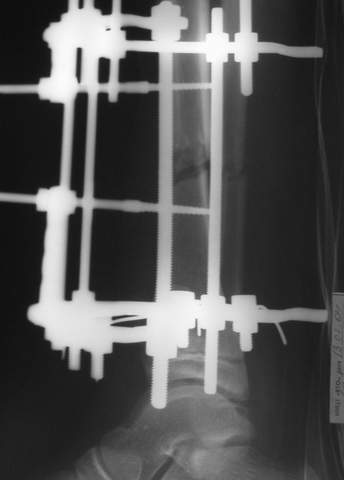

Под рукой прилагаемый пример. Как видите, "стриптиз-аппарат" (шутка проф. З.К.Башурова): 3 кольца-2 кольца-2 полукольца. В случае, который представил Евгений, характер повреждения позволил бы сразу использовать аппарат на основе 2 колец; в крайнем случае прокс. опора м.б. демонтирована сразу после репозиции.

В аттачтах №№ 1 и 2 - примеры, когда 2 кольца не позволили послеоперационно

исправить смещение фрагментов большеберцовой (по ширине и вальгусное).

А казалось бы (#2) - поиграй на штангах и все влетит.

1

1a